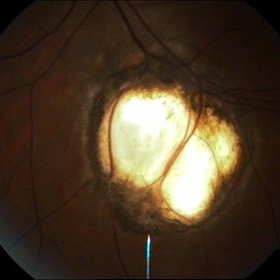

Optic Nerve Head Avulsion

Sep 15 2014 by Mehul A Shah

A 30-year-old male patient met vehicular accident and found to have optic nerve head avulsion with scarring.

Photographer: Drashti Netralaya,Dahod

Imaging device: Zeiss ff450

Condition/keywords: optic nerve head avulsion